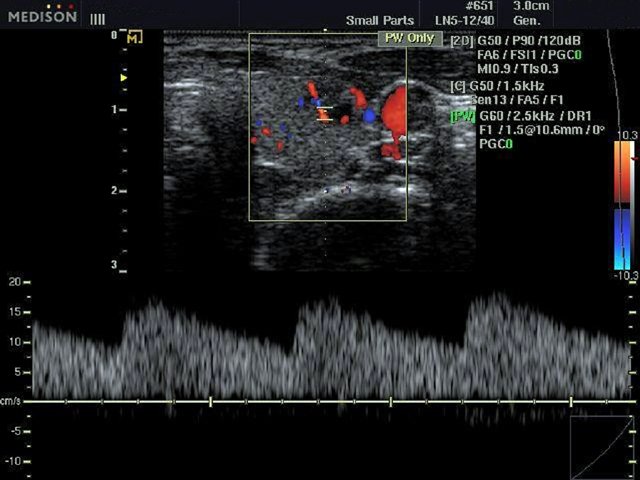

[RU] Ultrasound image №482: Thyroid blood flow in color doppler mode (CFM).

Echogramm was received by ultrasound scanner SonoAce-R3 (out of production).